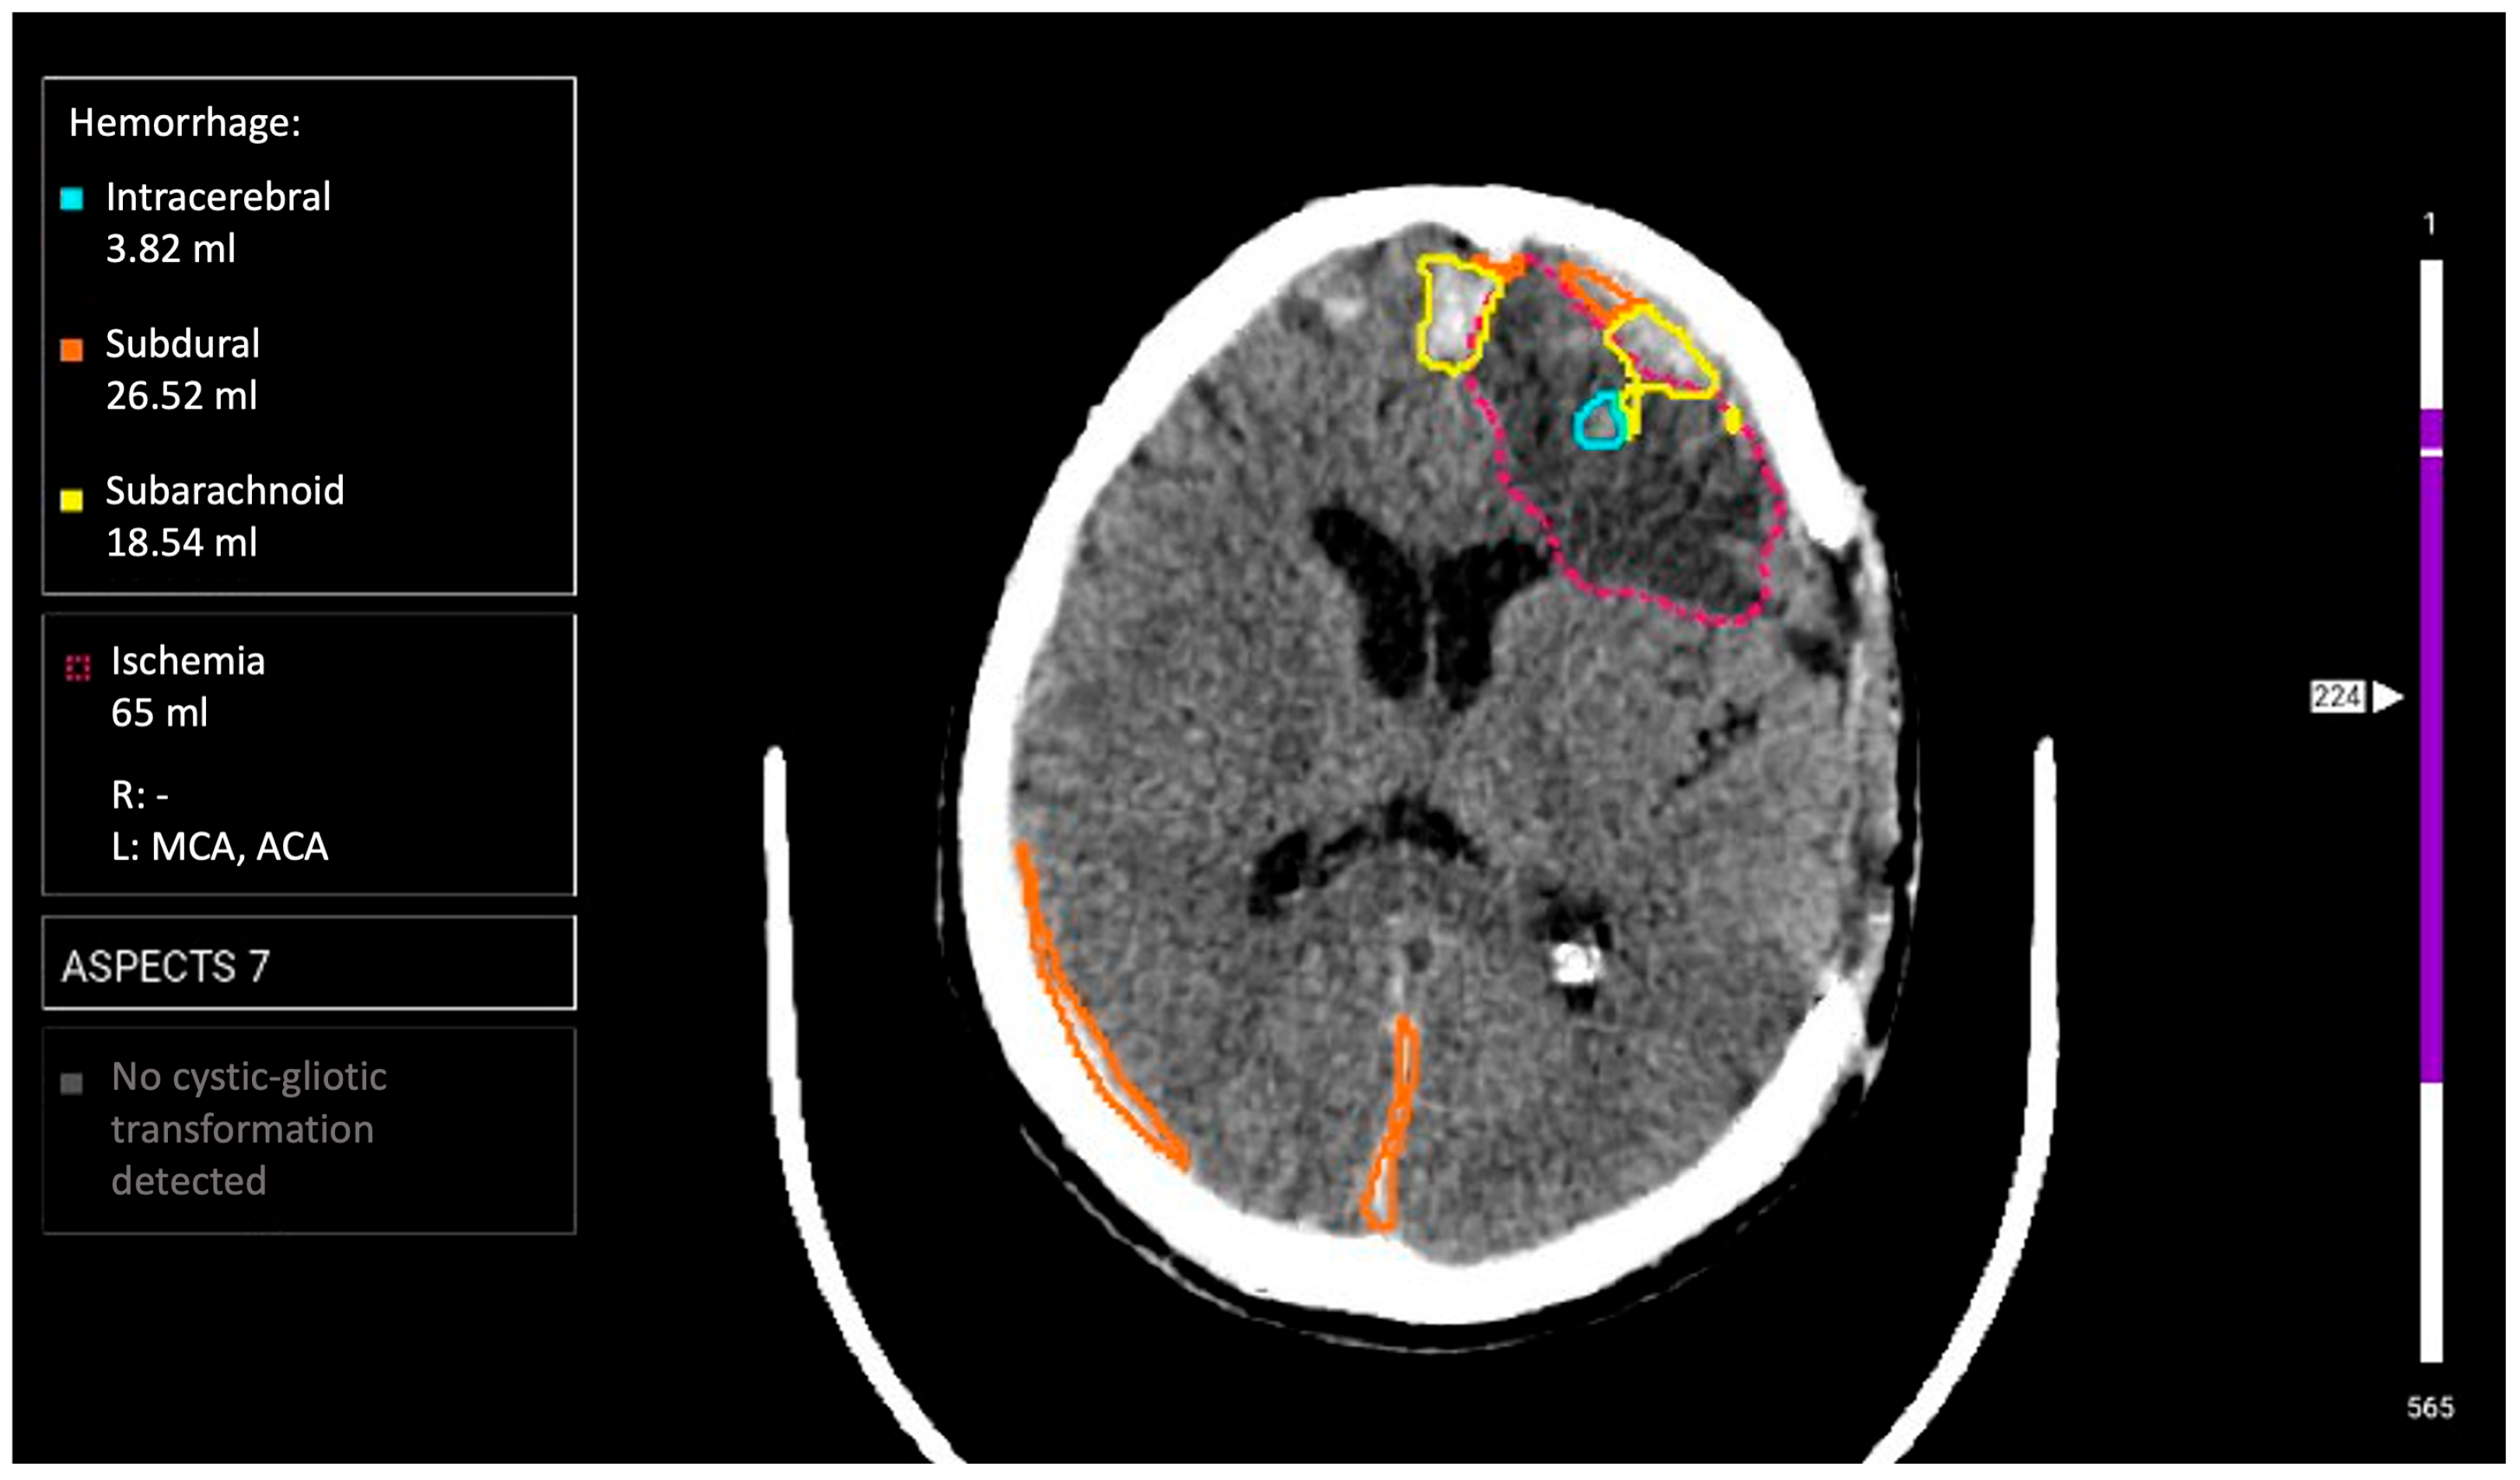

- Hyperdense foci in brain parenchyma, meningeal spaces, or ventricular system (epidural, subdural, subarachnoid, and intracerebral localization);

- Density > 40 HU for acute hemorrhages;

- Complete correspondence: AI conclusion fully matches expert opinion (both for normal cases and pathology presence);

- Partially correct assessment: pathology presence confirmation with description disagreements (e.g., intracerebral interpreted as subarachnoid hemorrhage, etc.);

- False-positive result: AI indicated pathology rejected by expert;

- False-negative result: AI missed pathology confirmed by expert.